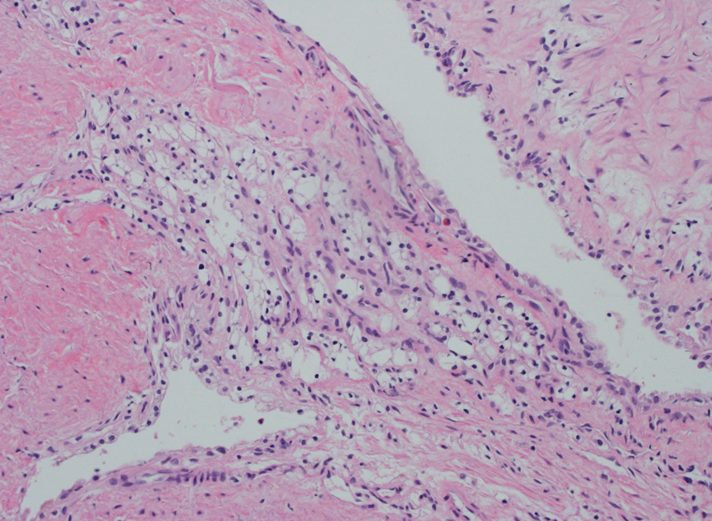

Renal tumor grading

Case ID: 653